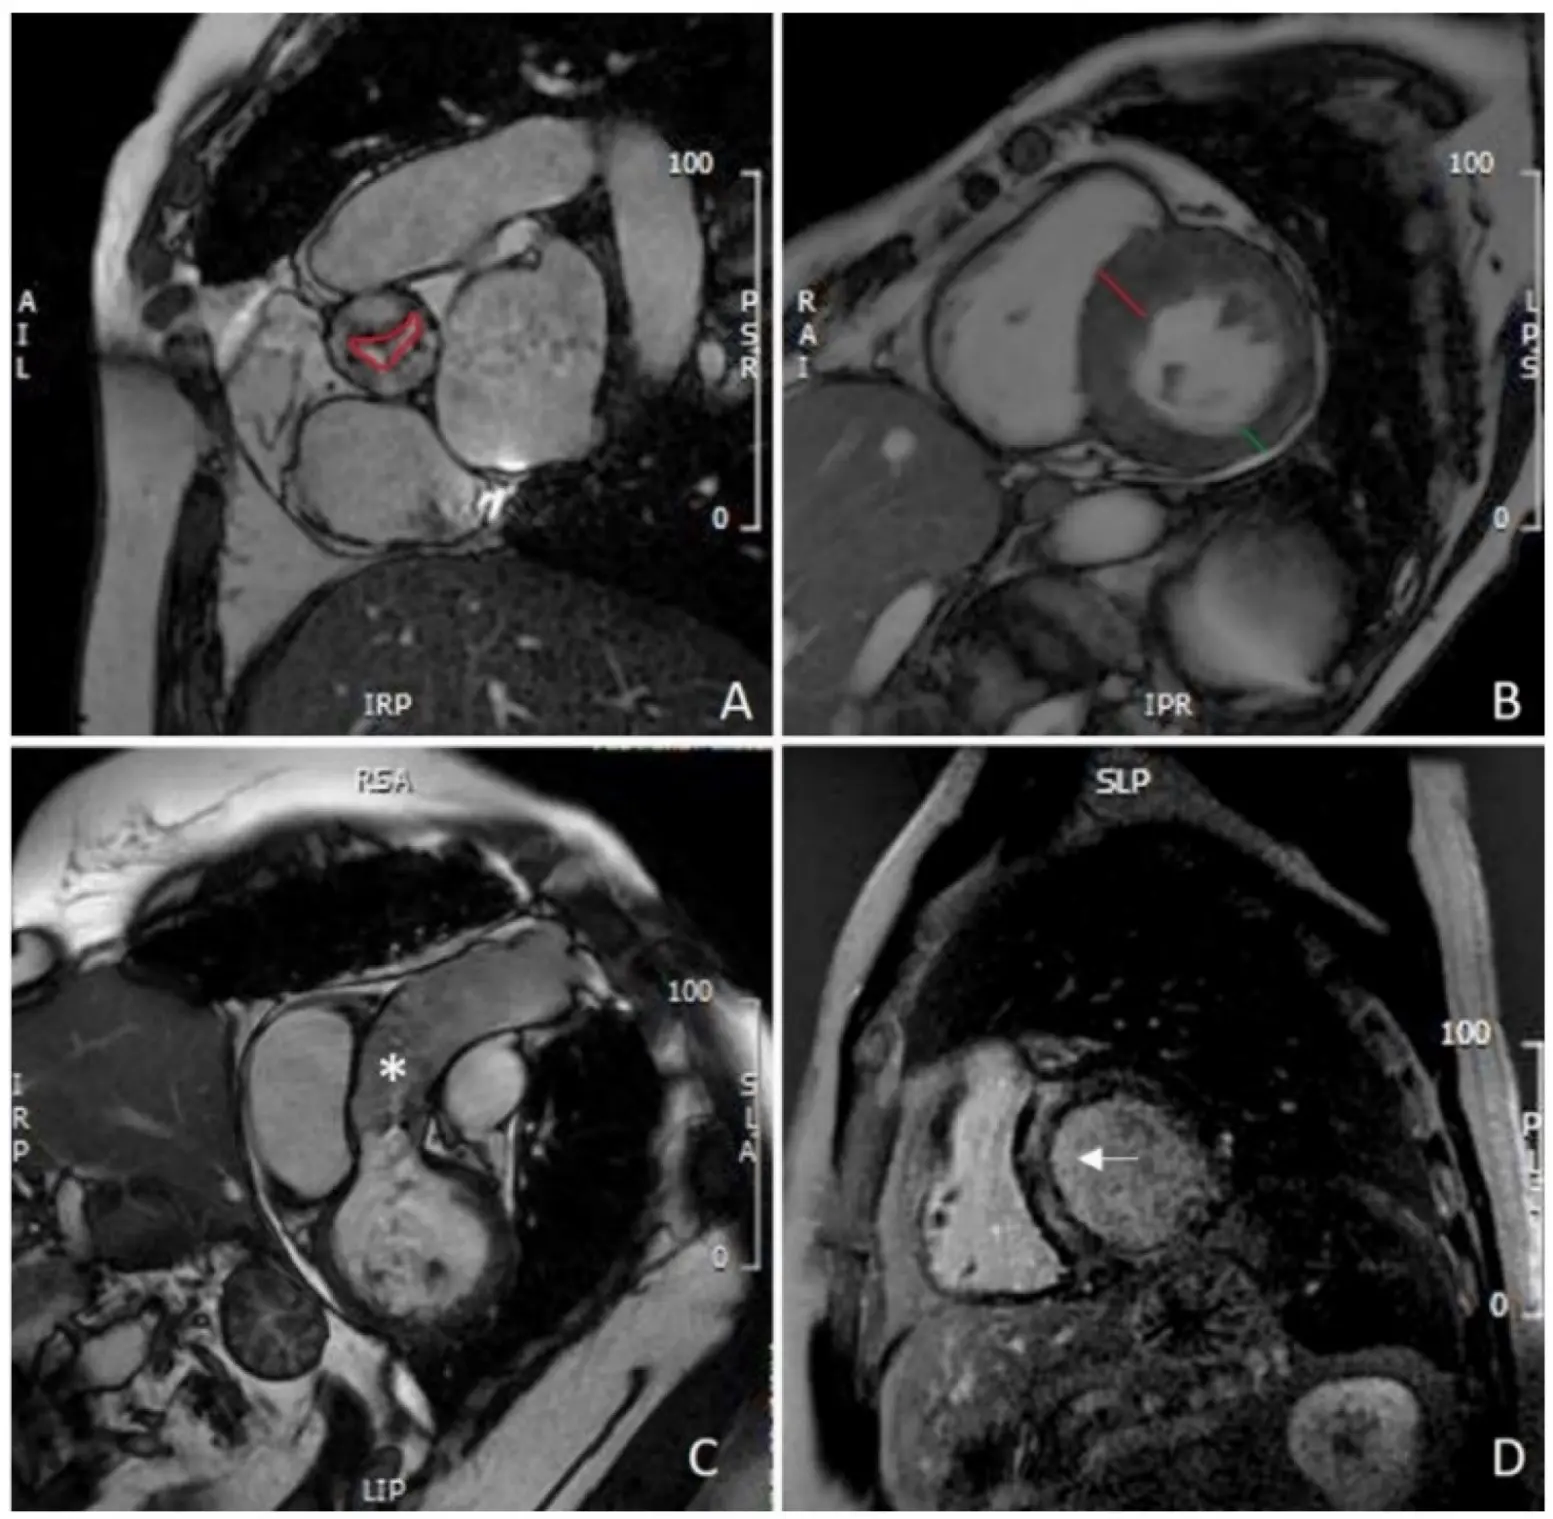

Beyond diagnostic evaluation, CMR-derived tissue characterization carries major prognostic value in AS. Late gadolinium enhancement (LGE) identifies focal replacement (often midwall) fibrosis (Figure 3), an irreversible injury pattern, whose presence independently predicts mortality beyond valve severity and LVEF; in a multicenter cohort, midwall LGE remained an independent predictor of all-cause death and added incremental risk-stratification value [49]. Quantitative T1-mapping indices of diffuse interstitial fibrosis (native T1 and extracellular volume fraction, ECV) capture earlier myocardial disease; in an international multicenter JACC study, higher ECV showed stepwise increases in mortality across tertiles and was independently associated with all-cause mortality after adjustment for age, sex, LVEF, and LGE [50]. Together, LGE (presence/extent) and elevated ECV provide complementary, incremental prognostic information beyond conventional hemodynamic indices, inform timing of intervention, and help anticipate reverse remodeling after AVR.

Figure 3. CMR evaluation of aortic stenosis: (A) planimetry of aortic valve (red line); (B) measurement of IVS (red line) and PW thickening (green line), showing asymmetric hypertrophy of the IVS; (C) assessment of thoracic aorta (asterisk); (D) mid-wall LGE of the IVS (white arrow). CMR: cardiovascular magnetic resonance; IVS: interventricular septum; PW: left ventricle posterolateral wall; LGE: late gadolinium enhancement.